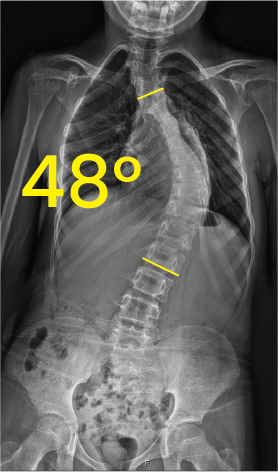

X-ray image of a human torso showing a 48-degree spinal curvature indicative of scoliosis.X-ray image of a spine showing scoliosis with a 38-degree curvature marked between two yellow lines.